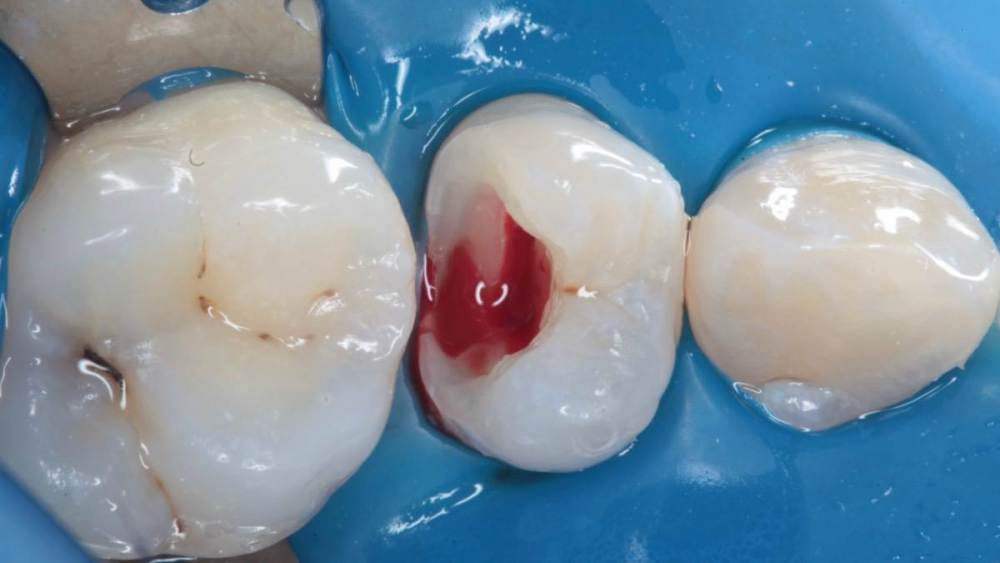

Гарриевич Опубликовано 21 мая, 2022 Поделиться Опубликовано 21 мая, 2022 (изменено) Будущее за регенеративной эндодонтией?) лечение в 2 посещения из-за нехватки времени (новый ассистент, перегруз пациентами, мысли о поднятии стоимости лечения, гипердиагностика?) глубокая пульпотомия, триоксидент, композит. фото подробно выложил это снимок с временной пломбой мало ли что вы подумаете Изменено 21 мая, 2022 пользователем Гарриевич 1 Ссылка на комментарий